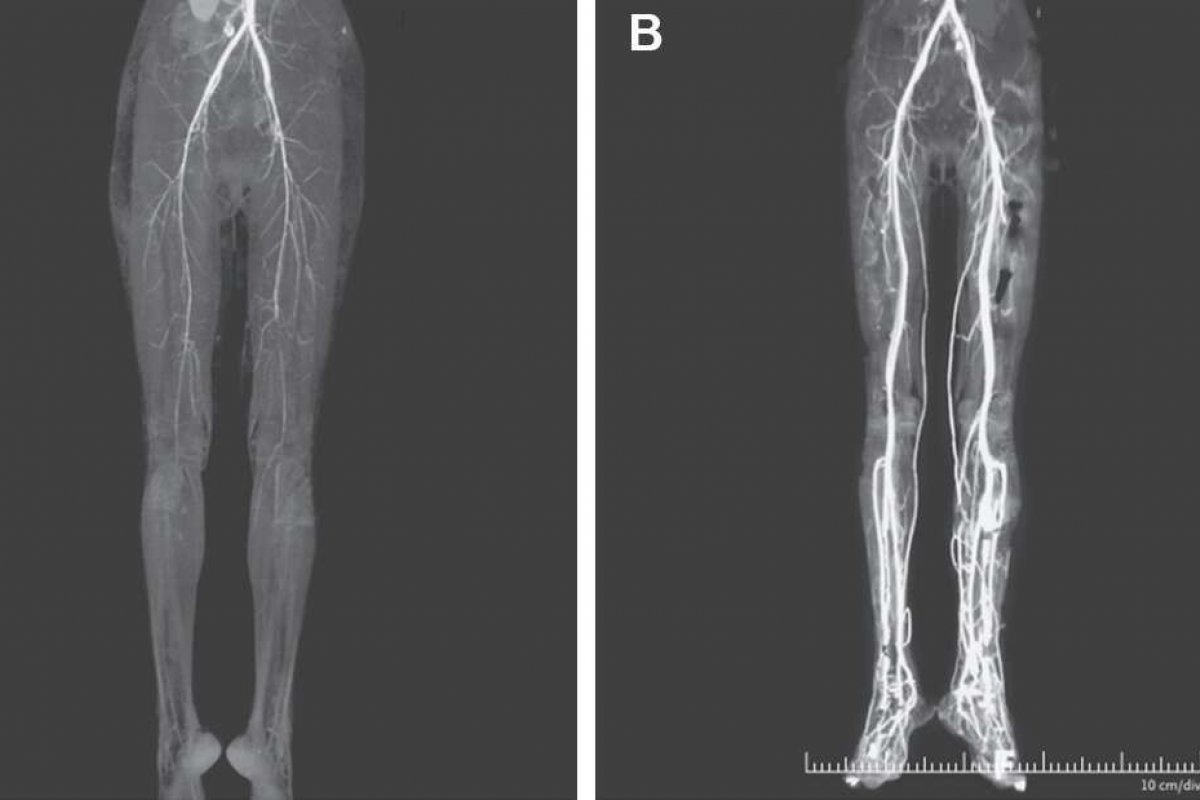

Segundo os médicos, a mulher contou que sentia queimação nas pernas e que se entendia dos dedos dos pés até o meio das coxas, além da descoloração da cor da pele e dificuldade para andar. "A angiotomografia computadorizada (TC) revelou o estreitamento (...) das artérias nas duas pernas", explicam no artigo.

Depois do tratamento, o fluxo sanguíneo nas duas pernas retornou e ela pôde se recuperar.